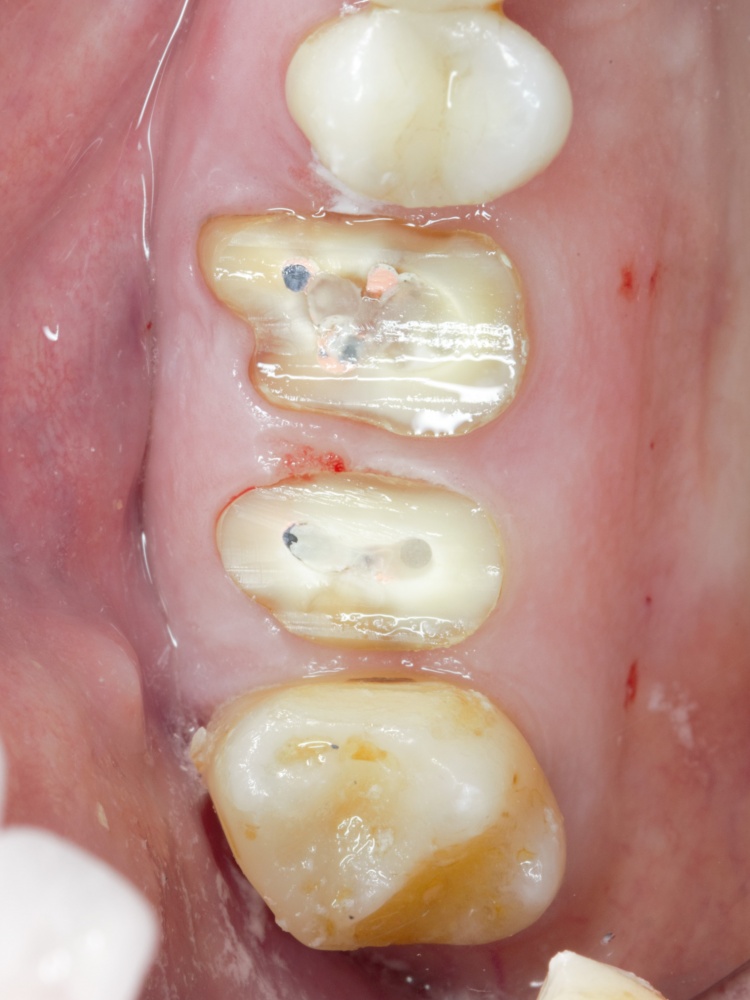

Простой синуслифтинг. Часть I.